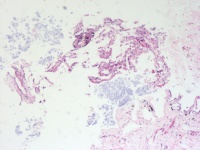

CT示左肺节段性肺不张 合并占位 既往有前列腺Ca病史

肺穿刺活检

0.5*0.3*0.2cm灰红碎组织

老师您好,这几个图片貌似没有恶性病变呀

慢性炎。